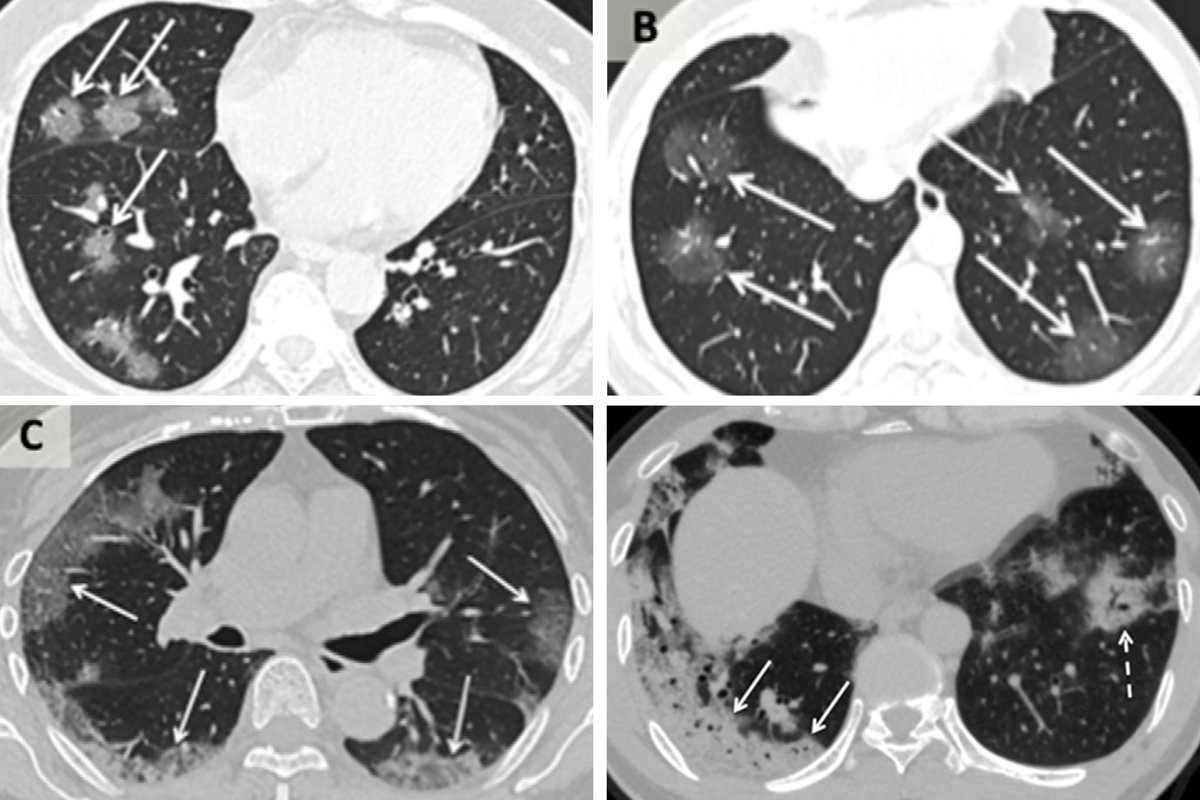

Tüm dünyaya yayılan ve milyonlarca insana bulaşan koronavirüsün vücutta neden olduğu tahribatla ilgili ABD’li bilim insanları çarpıcı bir açıklamada bulundu.

Teksas’ta bulunan Teksas Teknoloji Üniversitesi Sağlık Bilimleri Merkezi’nde Doç. Dr. Britatany Bankhead-Kendall, Kovid-19’a yakalanmış hastalarının akciğer filmini sigara içen biri ve sağlıklı bir kişinin filmleriyle karşılaştırdı.

Karşılaştırılan röntgen sonuçları büyük dikkat çekti. En soldaki görselde sigara içen bir bireyin akciğer filmi görülürken sağdaki filmde ise Kovid-19’u yenmiş bir bireyinki bulunuyor.

Akciğer filminde siyah alanlar ne kadar fazla ise o kişinin ciğer kapasitesi ve sağlığı o kadar iyi demektir. Beyaz kısımların artması ise akciğerin kapasitesinin azaldığı anlamını taşır.

Karşılaştırılan röntgen sonuçlarıyla Kovid-19’u geçirmiş ve sağlığına kavuşmuş kişilerin ciğerlerinde görülen hasarın sigara bağımlısı olan kişilerden çok daha kötü olduğunu gözler önüne seren Bankhead-Kendall, ‘Sağlıklı bir bireyin röntgen sonucunda siyah alan büyük olur. Bu da o kişinin ciğerlerine alabileceği oksijen seviyesini gösterir.

Sigara içenlerde hafif hareler yer alırken Covid-19 hastalarının ciğerleri ise bembeyazdır. Yani bu da koronavirüsü yenenlerde bile akciğer sorunları yaşanabildiğini gösteriyor’ açıklamasında bulundu.